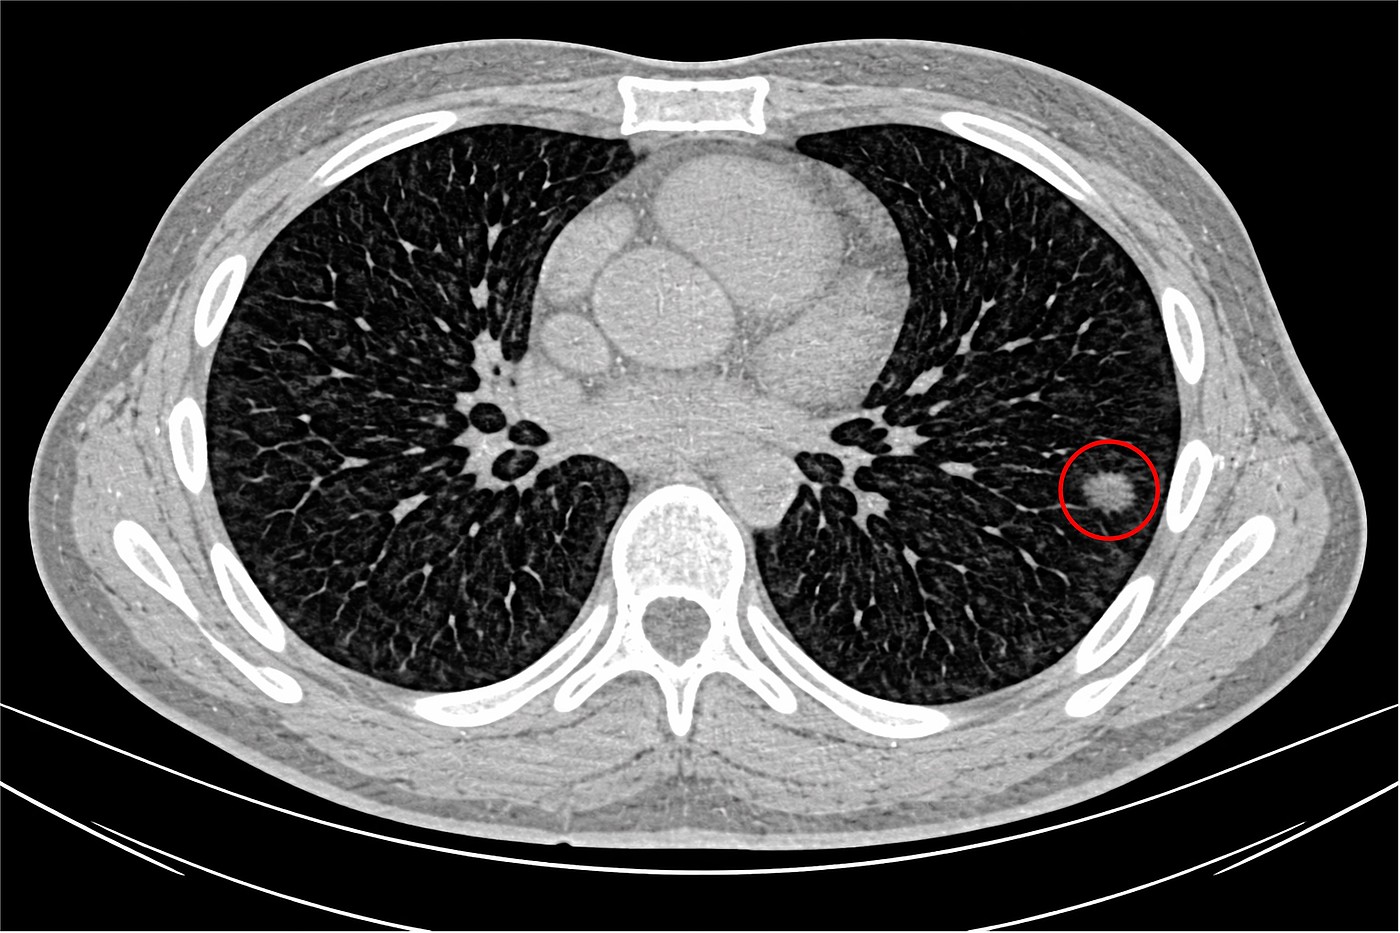

Wird eine Computertomographie (CT) des Brustkorbs zur Abklärung einer Lungen- oder Herzerkrankung durchgeführt, finden sich häufig so genannte Lungenrundherde als Zufallsbefund. Hierbei handelt es sich um rundliche scharf begrenzte Verschattungen bis zu einem Durchmesser von 3 cm, die dichter als das umgebende Lungengewebe erscheinen. Lungenrundherde verursachen in der Regel keine Beschwerden und haben glücklicherweise häufig harmlose Ursachen, die keiner Behandlung bedürfen. Dennoch kann es sich bei einem Lungenrundherd prinzipiell auch um das frühe Stadium einer bösartigen Erkrankung, insbesondere Lungenkrebs handeln.